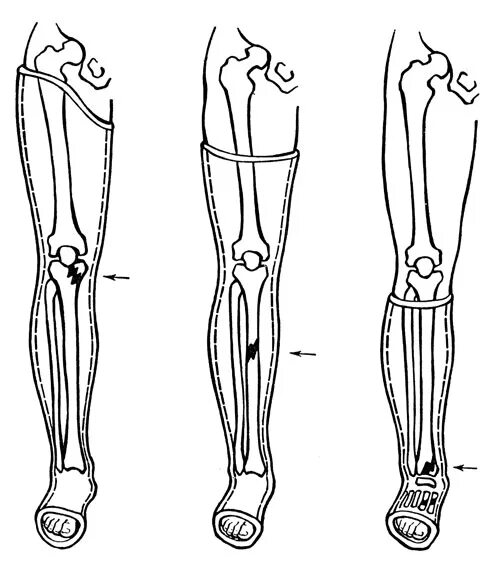

Перелом берцовой кости как разработать